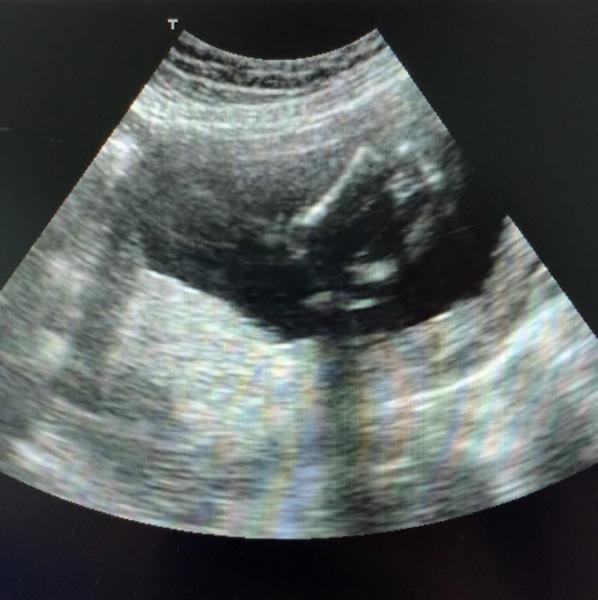

Ich habe ein US Bild von meiner FA bekommen und denke, dass man das Geschlecht vl erkennen kann... aber sie hat nichts weiter dazu gesagt. Hat jemand ein ähnliches Bild bekommen und weiß es genau??

Bild zu Geschlecht erkennbar?Hat jemand Erfahrung? - Schwanger - wer noch? Rund um die Schwangerschaft

Hm, es ist ein Bild von unten, man sieht die Beine links u rechts und darum dachte ich die drei Striche deuten auf eine Vagina hin..

Ich sehe auch die "Kaffeebohne". Alles Gute

Ich sehe leider keine 3 Striche. Dachte eher an einen Jungen aber das Bild ist echt nicht gut